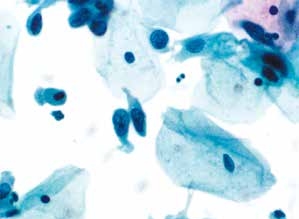

图4-2 非典型鳞状细胞,意义不明确(ASC-US)(高倍、液基、巴氏染色)

细胞核略增大(与中层鳞状上皮细胞核相比),形状略不规则,染色质稍深染,颗粒微粗。